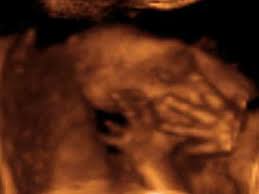

Ya sabes el sexo de tu bebé, en estas semanas comenzarán a desarrollarse sus órganos sexuales. Si al finalizar el séptimo mes te realizas una ecografía en 4D verás que tu bebé gesticula, sonríe, está triste, verás que los músculos de su cara se mueven, se chupa el dedo. Una linda experiencia que puedes vivir a semanas de que nazca.

ECOGRAFIA 4D